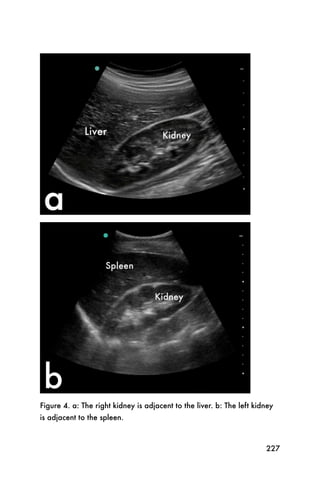

children and young adults. They are usually solitary

lesions surrounded by thin epithelium. A pure cyst will

appear spherical, darkly anechoic, and have well-